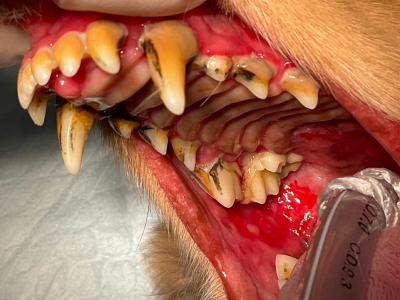

術前

歯周病は中程度ですが…頬の奥がただれています。

-